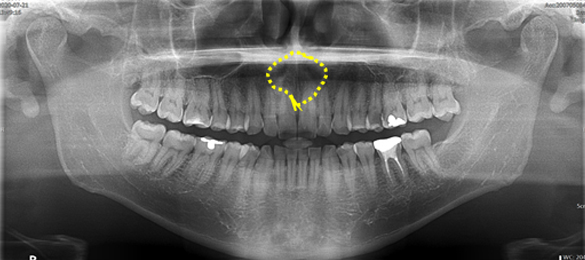

01. 턱뼈의 물주머니

함치성낭종 (Dentigerous cyst)

매복된 사랑니 머리 주변에서 발생하는

가장 흔한 턱뼈의 물주머니입니다.

신경관과 닿아 있어 CT 촬영이 필요하고

수술과 조직 검사를 반드시 해야 합니다.

파노라마 방사선 사진